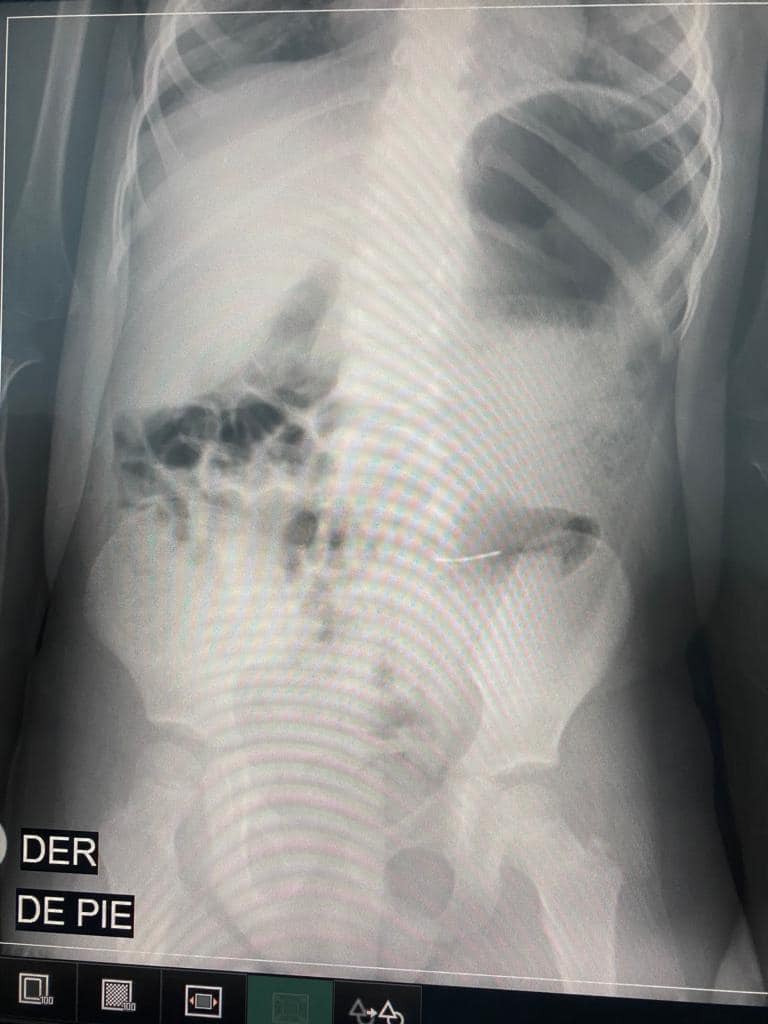

„ Днес дъщерите ми ядаха от тортата, уверени, че всичко в нея е годно за консумация. Изядаха си частите и в този момент имат метал в коремите си. Прилагам фотографията на тортата по какъв начин изглеждаше, когато пристигна и рентгеновите фотоси с метала в стомаха.“

„ Рождения ден от ден за тържество за моята Марифер (Мария Фернанда) завърши в болничното заведение, с цел да я държим под наблюдаване и да сме сигурни, че всичко е наред. Все още не е ясно какво ще се случи, дали ще се наложи интервенция или самичък ще излезе метала.“